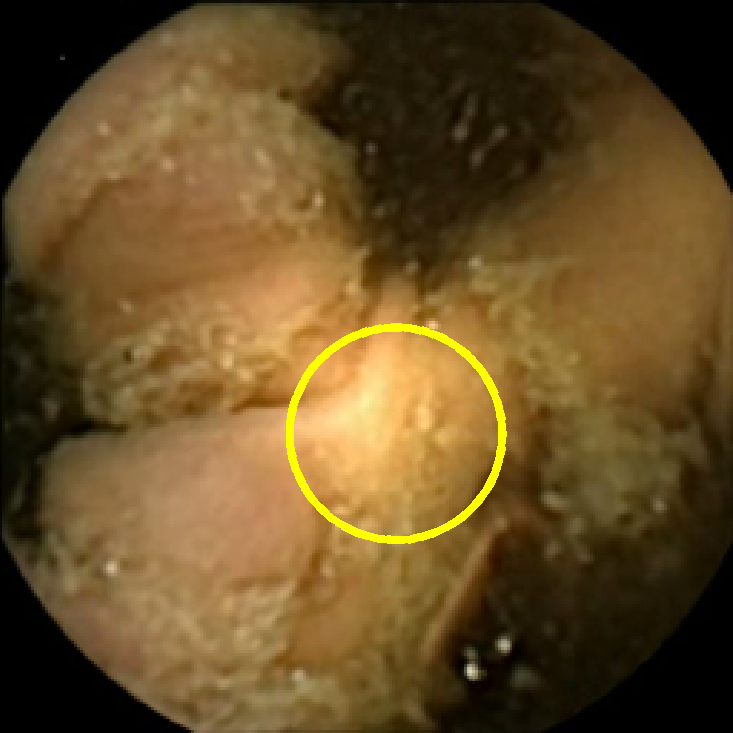

We illustrate the above considerations in Figure 4, where we compare the ellipses of inertia for a polyp frame and two frames with pronounced mucosal folds. The ellipses we plot are

| (20) |

where . The scaling term in front of is chosen so that the area of the ellipse of inertia is the same as the size of the corresponding feature.

As expected, we observe that the ellipses corresponding to mucosal folds (feature 2 in the second row and features 2 and 3 in the third row of Figure 4) are indeed much more stretched out than the ellipse corresponding to a polyp (feature 1 in the first row of Figure 4). Stretched ellipses imply higher eccentricity, thus we impose the following criterion

| (21) |

with some threshold to select moderately stretched features that are more likely to correspond to polyps.